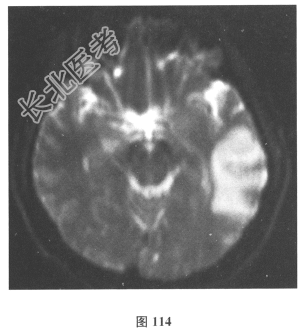

- 简答题2、脑脊液检查:常规、生化均正常,CSF-病毒TORCH(-),抗Hu、Yo、Ri均阴性,OB、MBP正常。血清抗Hu、Yo、Ri均阴性。颅脑MRI显示左颞枕、右顶枕多发长T₁、长T₂信号,Flair高信号,病变累及皮质及皮质下白质,病灶无强化,见图108~图114。)根据颅脑MRI,需要鉴别的疾病应是